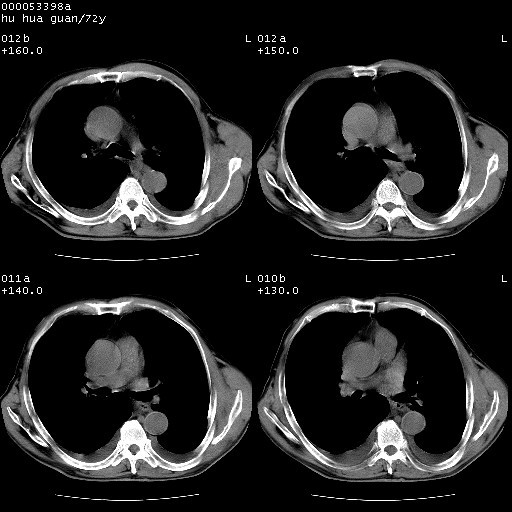

标题: CT15582:M,72Y。请老师帮分析胸部病变。

可以明确的说。肯定不是主动脉夹层破裂出血!考虑为淋巴瘤或间叶组织来源的恶性肿瘤可能性大。右肺小结节建议薄层观察,如能发现恶性征象,那椎前改变就考虑为转移所致。至于双侧少量胸水乃静脉血回流受阻所致。

1、右肺周围性肺癌、胸腔积液(双)

1、右上肺结节病变,肺泡癌不除外,请随诊;左下肺近后纵隔病变,考虑纵隔型肺癌侵犯大血管可能;

降主动脉前移位,后纵隔占位

后纵隔占位,降主动脉前移位;双侧胸腔积液;应排外食管病变侵犯血管可能;